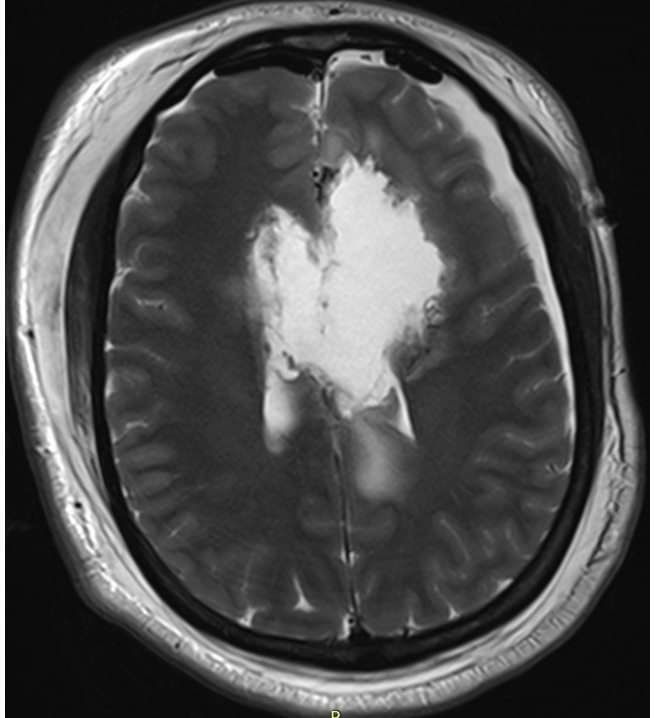

Чуть больше месяца назад в отделение поступила девушка 33 лет с жалобами на периодическую головную боль и однократный эпизод утраты сознания. При МРТ головного мозга выявлена большая опухоль обеих лобных долей с поражением мозолистого тела, размером 11,1х6,5х7,5см. (объем 283,3см3). Основной массив опухоли локализовался в левой лобной доле, подходя вплотную к зонам на коре, отвечающим за движения в правых конечностях и за произношение слов. В глубине опухоль находилась в непосредственной близости от речевых трактов и пирамидных трактов с двух сторон. Повреждение их могло привести к нарушениям речи или парализации пациентки. Мозолистое тело (структура, которая соединяет два полушария мозга между собой) было поражено опухолью на 75%. Разобщение полушарий (пересечение мозолистого тела) может привести к выраженным психическим нарушениям. В структуре опухоли проходили крупные сосуды, питающие до 30% полушарий. Все это делало предстоящую операцию действительно сложной. Так же напрягало еще то, что больную кроме умеренной головной боли ничего больше не беспокоило.

На послеоперационных МРТ видно, что опухоль удалена на 98,3%. Небольшой ее фрагмент в задних отделах пришлось оставить из-за прорастания ей двигательных зон.